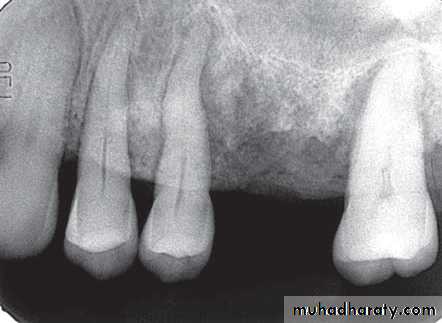

Location: Apex of involved tooth / Cervically up the tooth root.Periphery: Ill defined / Well defined, with gradual blending of normal trabecular pattern into sclerotic pattern.

*Widening of PDL space at the apex.

*A mixture of sclerosis (radiopaque) and rarefaction (radiolucent).

* ↑se bone formation → periapical sclerosing osteitis.

*↑se bone resorption → periapical rarefying osteitis.

* Losing of lamina dura at the apex.* Regions of sclerotic bone around apex.

* External apical root resorption.